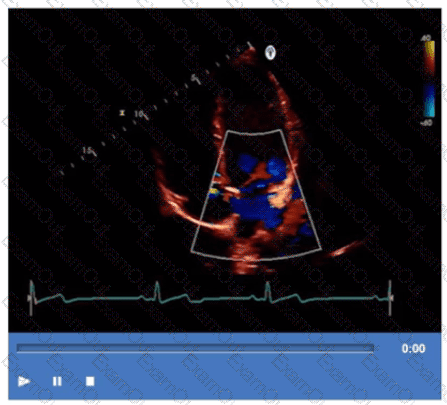

Which mitral regurgitation jet direction is most consistent with hypertrophic obstructive cardiomyopathy?